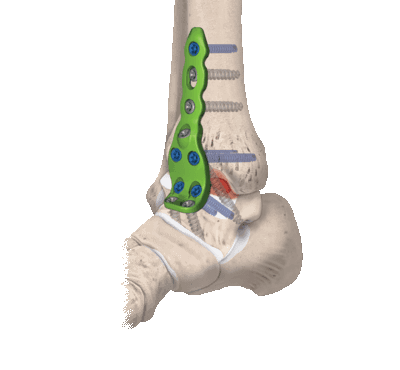

- Для оперативного лечения повреждений медиальной лодыжки наиболее предпочтителен медиальный доступ, ввиду его соответствия необходимым требованиям.

- Для оперативного лечения повреждений латеральной лодыжки наиболее предпочтителен латеральный доступ, так как частота осложнений при выполнении данного оперативного доступа минимальна.

- Для оперативного лечения бималлеолярного и трималлеолярного переломов наиболее предпочтительна комбинация медиального и латерального доступов, что обеспечивает лучшую визуализацию медиальной, латеральной и передней колонн и больший объём маневра во время операции.